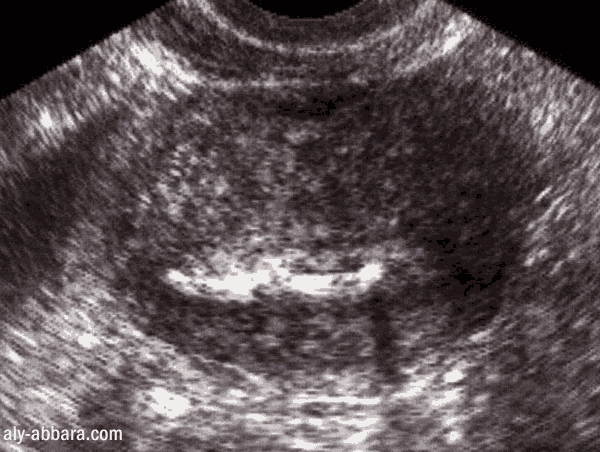

L'emplacement dans l'utérus vu par l'échographie

La branche horizontale du stérilet (coupe transversale sur l'utérus)